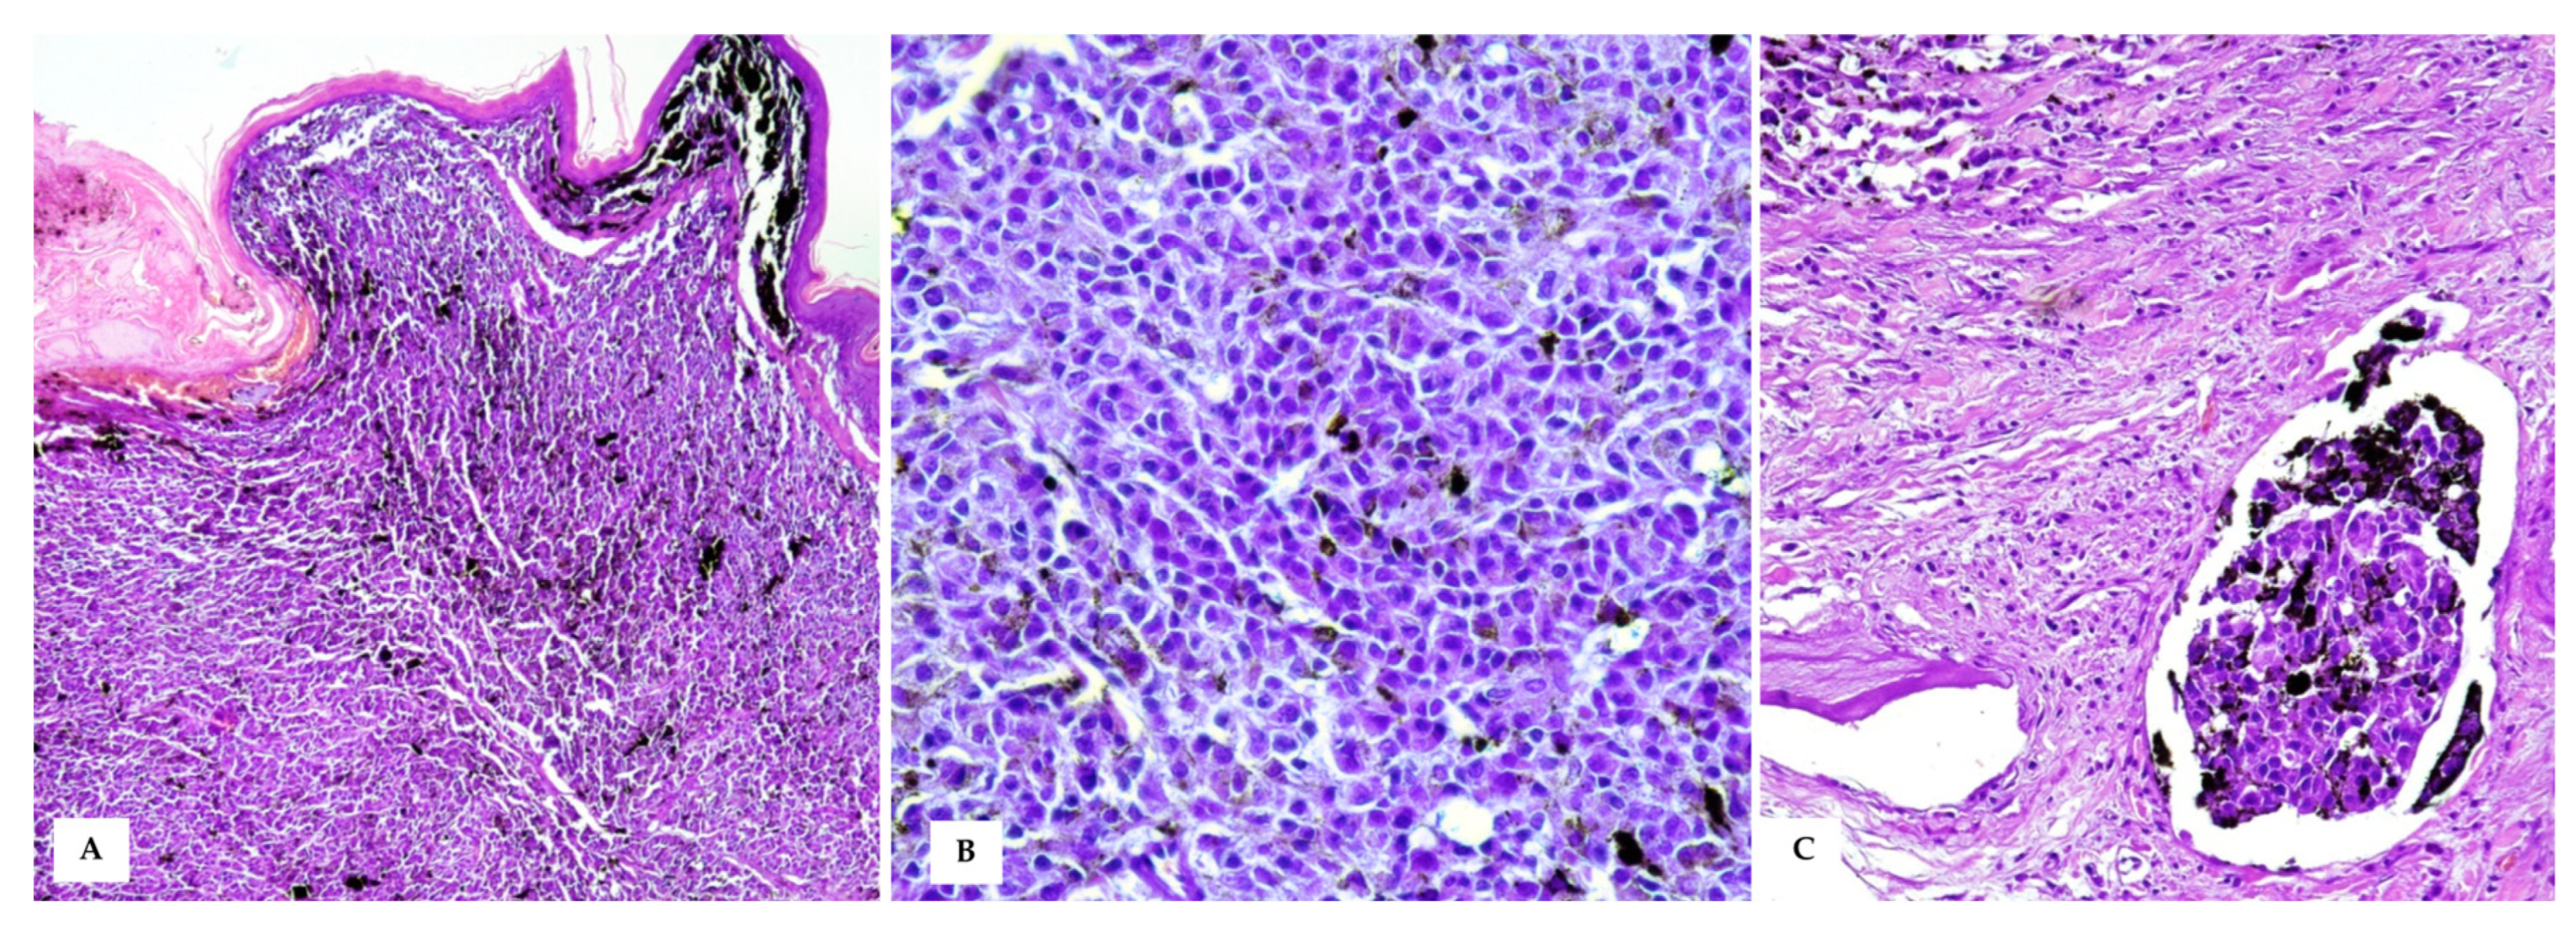

In HE-stained sections, a moderately demarcated, nonencapsulated, infiltrative, densely cellular neoplasm was observed, markedly expanding the dermis and elevating the multifocal ulcerated epidermis, covered by numerous serocellular crusts. The neoplasm was composed of polygonal- to spindle-shaped neoplastic melanocytes arranged in nests and sheets, extending multifocally at the epidermal–dermal junction and supported by scant fibrovascular stroma. Neoplastic cells were 10–15 μm, with often distinct cell borders, intermediate N/C ratio, and moderate, slightly basophilic cytoplasm, often obscured by abundant brownish granular pigment (melanin). Nuclei were round and eccentric, with coarsely stippled chromatin and 1–2 prominent nucleoli. Anisocytosis and anisokaryosis were marked, with karyomegaly, and multinucleated cells were occasionally observed. Mitoses were 18 in 10 high-power fields (400× magnification, 2.37 mm2). Diffuse dermal lymphovascular invasion was observed, as well as large areas of intratumoural colliquative necrosis and haemorrhage (Figure 4). Nuclear atypia was >20% (i.e., 33%) [13].

Figure 4. Cutaneous Malignant Melanoma (A) A densely cellular neoplasm, markedly expands the dermis and reaches the dermo–epidermal junction, covered by intact or often ulcerated epidermis (HE, 20×); (B) At higher magnifications, the neoplastic cells show round to oval nuclei of varying size, moderate amount of cytoplasm with often large amounts of intracytoplasmic melanin, which obscures cellular details (HE, 40×). (C) Intratumoural lymphovascular invasion is evident (HE, 40×).